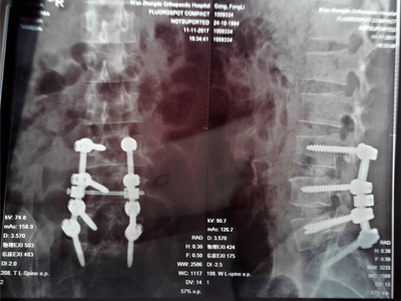

同时,腰椎CT示:腰4/5椎间盘膨出并右后型突出,腰5/骶1椎间盘膨出并左后型突出,左、右侧神经根受压。“患者坐骨神经疼,走不成路。”已严重影响日常生活,为恢复患者社会劳动能力,通过综合评估,决定立即行“腰3/4、4/5后路内固定、髓核摘除、椎管减压、神经根粘连松解、椎间隙植骨融合术”,术前、术中联合内科等多科室并行监管,经过2小时手术完成,术后恢复良好,患者满意。